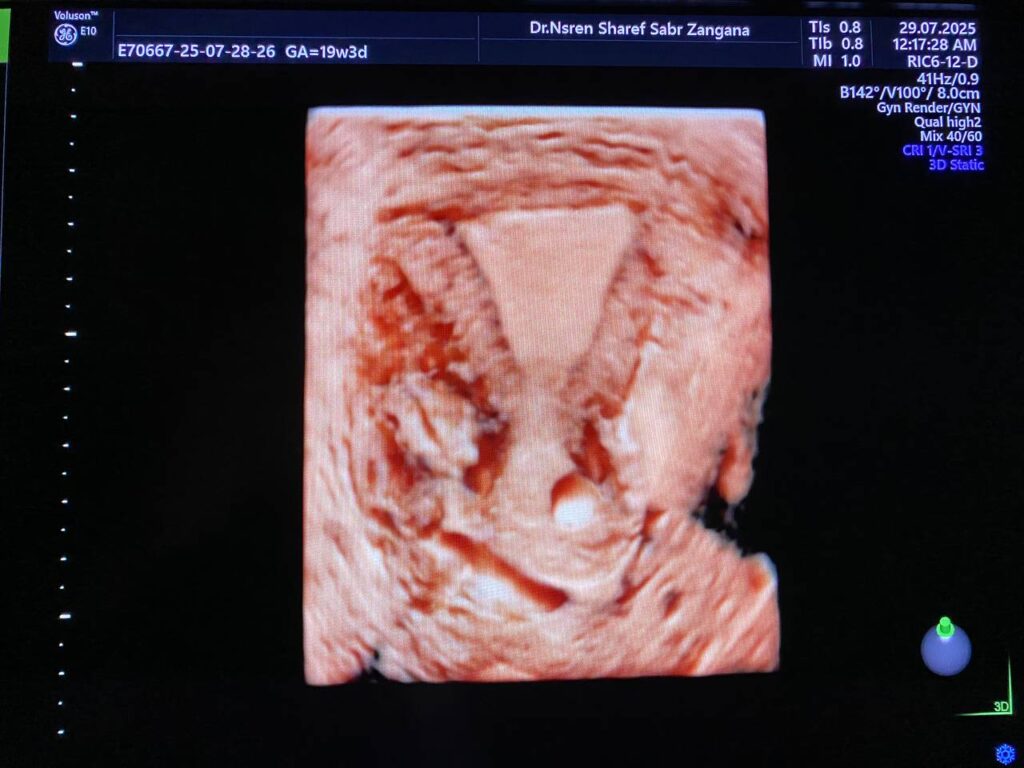

Bulky size A/V uterus, endometrial lining thickness 13mm, with presence of heterogenous cystic lesion in the right sided lower lateral body 22x2mm , mostly accessory cavity uterine malformation ACUM, no fibroid, single Nabothian cysts in the anterior lip of the cervix, its size11x8mm .